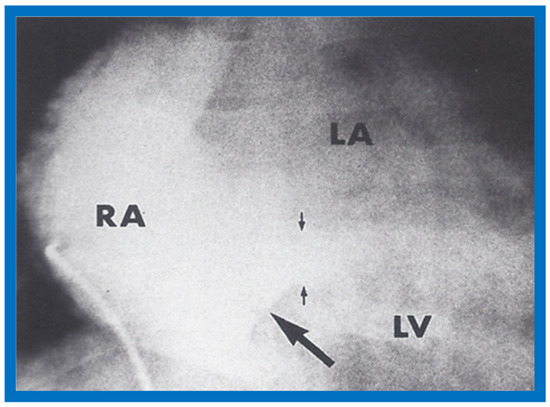

The author reported on the clinical, radiographic, ECG, echocardiographic and hemodynamic features of a rare case of common atrioventricular canal (currently called atrioventricular septal defect) mimicking tricuspid atresia in an eight-year-old child [15]. The clinical, radiographic and ECG characteristics were similar to those of classic tricuspid atresia. Hemodynamic data secured at cardiac catheterization were also similar to those seen with tricuspid atresia. A two-dimensional echocardiogram demonstrated an ostium primum atrial septal defect with a common atrioventricular valve and a small RV (Figure 50a,b); the entry into the RV appeared to be occluded by a leaflet of the common atrioventricular valve. Left ventricular cineangiogram in postero-anterior view demonstrated “gooseneck” deformity, similar to that seen in atrioventricular canal defects [15]. However, right atrial angiography resulted in direct emptying of the contrast material into the left ventricle via an ostium primum atrial septal defect (Figure 51). The floor of the right atrium seemed to be formed by a leaflet of the common atrioventricular valve (Figure 51). Thus, the two-dimensional echocardiographic and right atrial cineangiographic features appeared to be distinctive, and could be utilized to distinguish this anomaly from other varieties of tricuspid atresia.

Figure 50.

Selected two-dimensional, subcostal, four-chamber echocardiographic frames with an open (a) and closed (b) atrioventricular valve. Line drawings on the right of a and b are made for greater clarity and for labeling. A large ostium primum atrial septal defect (10 ASD) is shown in a. When the large atrioventricular valve leaflet is open (a), it completely closes the right ventricle (RV) from the right atrium (RA) and ventricular septal defect (VSD) and allows emptying of blood from both atria into the left ventricle (LV). When atrioventricular valve leaflet is closed (b), it continues to occlude the RV from the RA while allowing the VSD to freely communicate between RV and LV. Ap, Apex; AtTV, atretic tricuspid valve; Ba, base; L, left; LA, left atrium; R, right. Reproduced from Rao P.S. [15].

Figure 51.

Selected right atrial (RA) angiographic frame in postero-anterior view demonstrating that the floor of the right atrium is formed by one of the leaflets of the atrioventricular valve; this is marked by a large arrow. The contrast material exited the RA via an ostium primum atrial septal defect shown by small arrows with subsequent opacification of the left ventricle (LV). C, catheter; LA, left atrium. Reproduced from Rao P.S. [15].